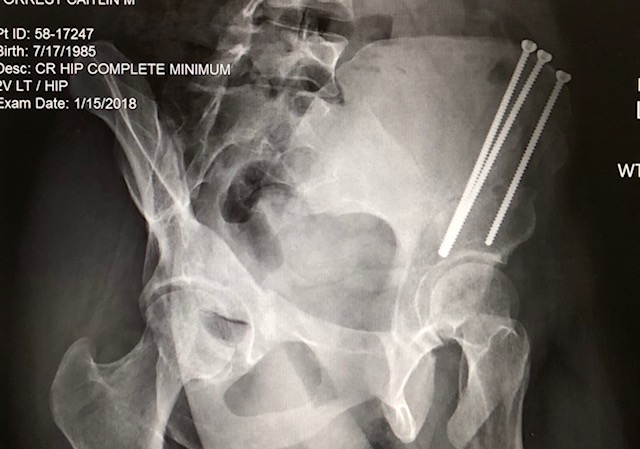

3 Months Post Op LPAO